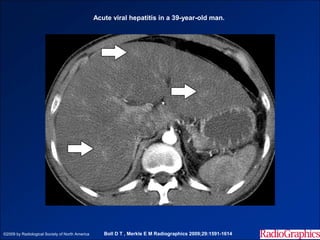

Hình ảnh trên CLVT

- Gan to, phù nền ở ngoại vi và bao gan.

- Trước tiêm, tỷ trọng nhu mô gan không đồng nhất, bằng

hoặc thấp hơn tỷ trọng lách.

- Sau tiêm, có vùng ngấm thuốc không đồng nhất.

- Phù nề quanh các nhánh TMC.

- Viêm gan mạn thường gây hậu quả xơ gan – bụng ascite và

lách to.

Acute viral hepatitis in a 39-year-old man.

©2009 by Radiological Society of North America      Boll D T , Merkle E M Radiographics 2009;29:1591-1614